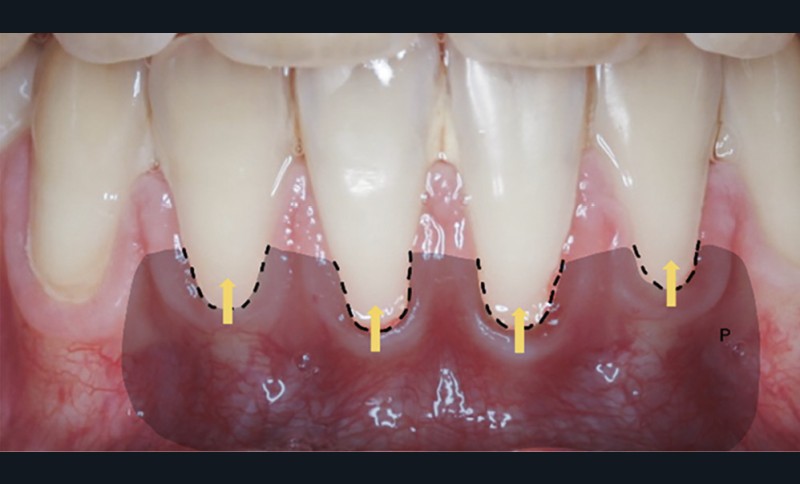

Concernant la terminologie, la classification de Cairo [6] détaille le type de récession.

La récession RT1 est une récession sans perte d’attache interproximale et où la JAC est cliniquement non détectable en zone interproximale, le recouvrement complet est possible. Lorsque la perte d’attache interproximale est inférieure ou égale à la perte d’attache vestibulaire, on parlera de récessions RT2, le recouvrement ne sera que partiel. La récession RT3 est une récession où la perte d’attache interproximale est supérieure à la perte d’attache vestibulaire, dans ce cas-là le recouvrement est impossible. Il est important aussi de savoir identifier et distinguer la récession gingivale de l’éruption passive incomplète qui est une anomalie de développement de l’éruption dentaire (fig. 1).